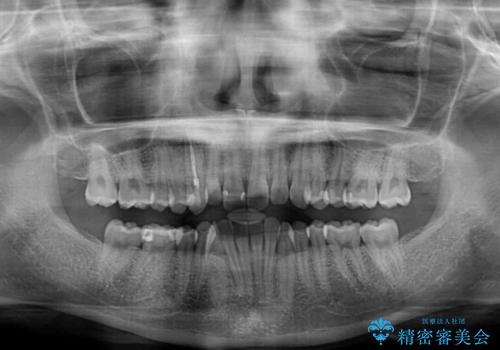

下顎前歯にデコボコが集中していたため、顎間ゴムによる後方移動とIPR(歯と歯の間を削ること)により歯列を整えることとしました。

矯正治療途中で右下奥歯の虫歯治療を近医で行ったようで、既に神経が失活していたと合わせて矯正治療後に補綴治療を行う予定です。